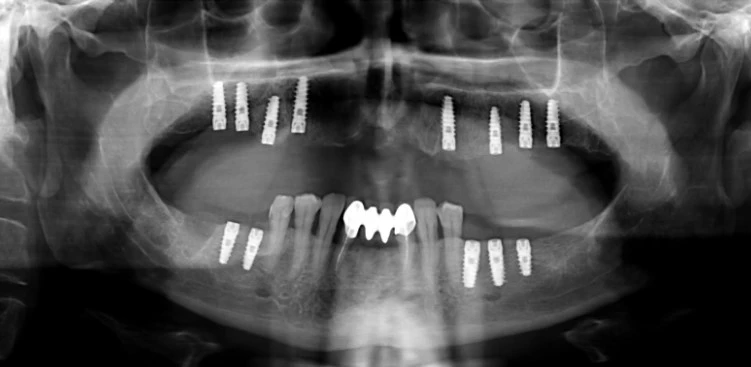

Третий этап — выбор типа протезирования. После анализа клинической ситуации стоматолог совместно с пациентом подбирает оптимальные варианты: это могут быть классические коронки, виниры, мостовидные протезы, либо современные дентальные импланты. Выбор зависит от локализации травмы, количества утраченных зубов, наличия противопоказаний и ожиданий пациента. Для передних зубов в Алматы часто выбирают керамические коронки и виниры, комбинируя эстетику и надежную фиксацию. В случае массивных повреждений или полной потери одного/нескольких зубов предпочтение отдается имплантации.

В сложных ситуациях, сопровождающихся значительной потерей костной ткани или множественными травмами, специалисты применяют комбинированные протоколы восстановления. Применение мини-имплантов, временных шинирующих систем и микропротезирования обеспечивает раннюю функциональность и поддержку десны. Классические протезы на основе металлокерамики постепенно уступают место безметалловым конструкциям и долговечным имплантатам, подход и выбор которых определяется не только клинической ситуацией, но и эстетическими требованиями пациента.

Имплантация зубов как золотой стандарт восстановления

Если говорить о долгосрочных решениях, лидером считается дентальная имплантация. Процедура предполагает установку искусственного корня, на который впоследствии фиксируется коронка, полностью воспроизводящая натуральный зуб. Жителям Алматы стоит обратить внимание, что в компании Benefakta Dental имплантация зубов под наркозом доступна для пациентов с разным уровнем тревожности и болевого порога имплантация зубов под наркозом обеспечивает не только безболезненность, но и сокращает время манипуляций, повышая эффективность восстановления.